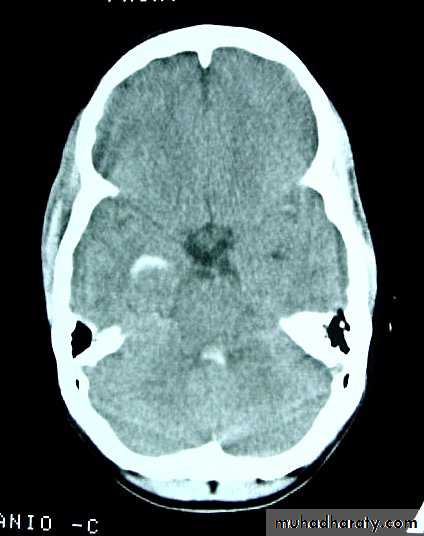

5. Hydrocephalus

a. Acutely due to obstruction of CSF outflow due to intraventricular blood.

b. Delayed post-traumatic communicating hydrocephalus due to impaired CSF reabsorption following traumatic subarachnoid haemorrhage

Intraventricular blood can lead to Hydrocephalus

Neurosurgery